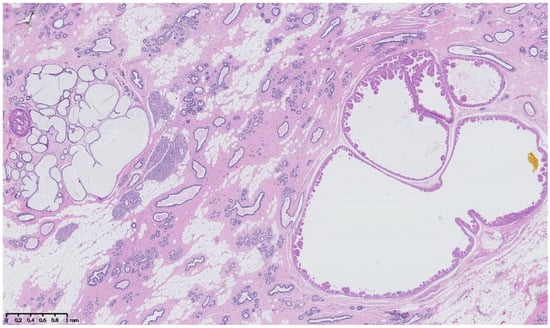

4. Benign Breast Lesions in Transwomen